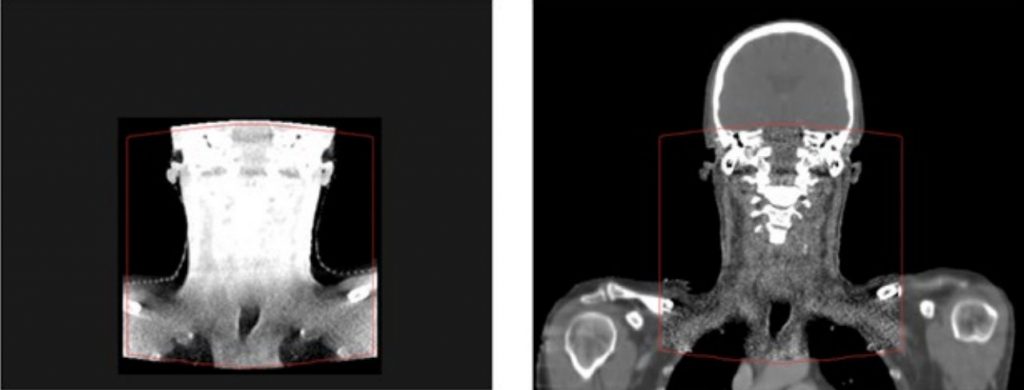

This method works for all CBCTs, with no calibration needed and no possibility of changes to the CBCT geometry. In case of limited FOV, parts outside the FOV are copied from the deformed planning CT to the CBCT.